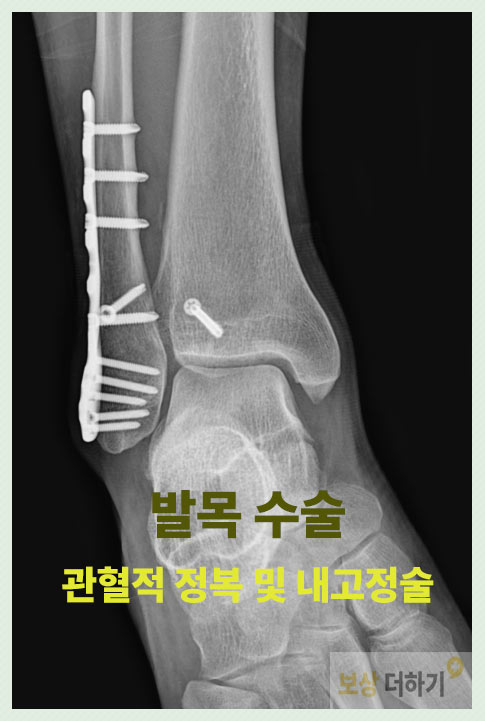

진단명 삼복사 골절, 발목, 폐쇄성 s82830

심각한 발목 손상이었기에, 골절 부위에 금속을 삽입하여 고정하는 관혈적 정복 및 내고정술이 시행되었습니다.